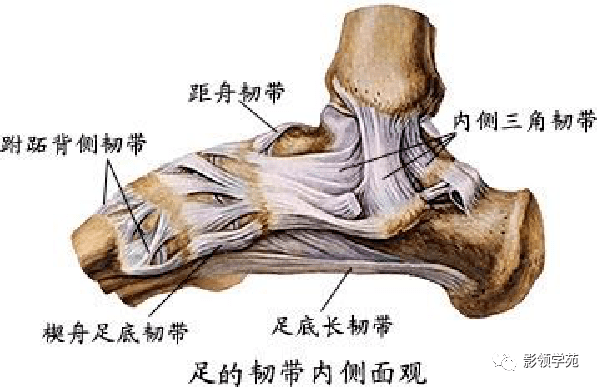

韧带系统

韧带系统